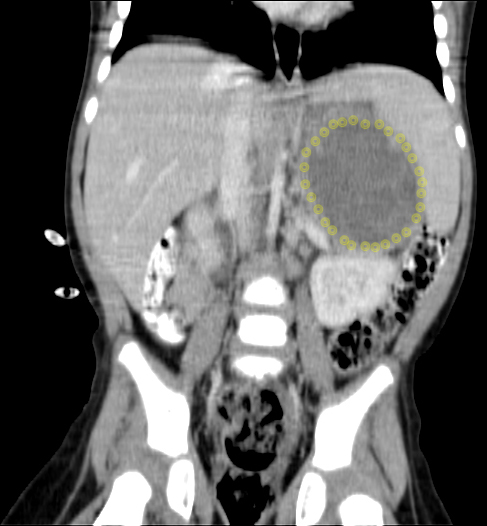

CT (CAT) scan 17July 2011